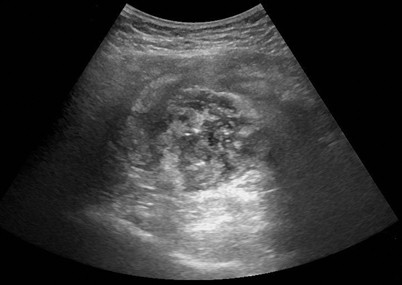

Akute Unterbauchschmerzen welche typischerweise zunächst in der Mitte des Bauches auftreten und dann im rechten Unterbauch zu spüren sind weisen auf das Vorliegen einer akuten Blinddarmentzündung hin. Zu den Symptomen von Leberkrebs zählen ein Druckschmerz im Oberbauch eine Schwellung unterhalb des rechten Rippenbogens Appetitlosigkeit Übelkeit erhöhte Temperatur ein allgemeines Schwächegefühl Leistungsminderung unbeabsichtigte Gewichtsabnahme sowie. Schwillt die Darmwand bei akuten Entzündungsschüben an sind die betroffenen Stellen meist druckschmerzempfindlich.

Viele andere Erkrankungen müssen noch ausgeschlossen werden. Doch ist dies bei Weitem nicht die einzige Ursache und Erkrankung bei Schmerzen im rechten BauchbereichGanz egal welche Ursachen die Bauchschmerzen haben es muss Abhilfe geschaffen. Schmerzen im Unterleib aus Muskeln Sehnen und Muskel-Faszien. Typisch für Schmerzen im rechten Unterbauch ist eine Blinddarmentzündung Appendizitis wobei hier entgegen der Bezeichnung gar nicht der Blinddarm selbst betroffen ist. Die Beschwerden lassen zunächst auch an eine chronische Blinddarmentzündung denken siehe oben. Allerdings ist ein Druckschmerz im rechten Unterbauch noch lange nicht beweisend für eine Appendizitis. Bei Frauen sollte bei Schmerzen im rechten Unterbauch.